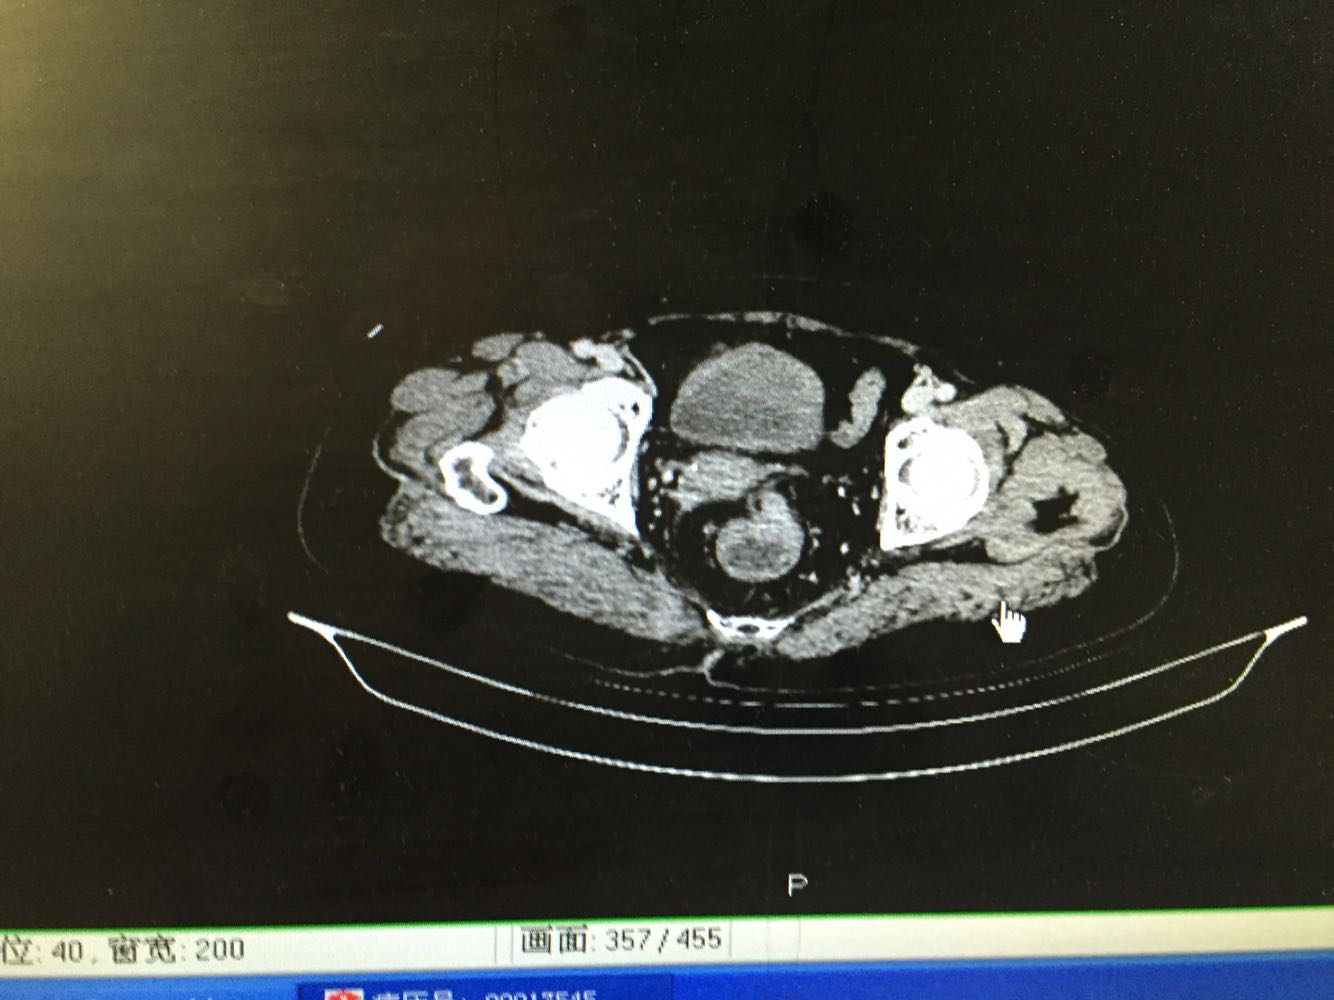

直肠指诊 距肛门7cm可及肿物下缘,环周生长,质偏硬。初诊直肠癌。病理提示高级别上皮内瘤变,未见平滑肌,浸润癌不排除。 腹部CT证实局段直肠癌厚,占位可考虑。

直肠占位明确,考虑活检深度不够,认为直肠癌可能性大。与患者家属商议后同意直接手术。行腹腔镜下直肠癌根治术。手术顺利,恢复满意。

患者病史比较长,一直未处理及治疗。术前阅片考虑外周侵润不明显,遂行腹腔镜手术,术后病理提示侵及深肌层,肠周淋巴结18枚均未见转移。 如果患者当初有症状及时就诊,可能并未癌变。基层见太多晚期肿瘤患者了。看病贵还是问题。